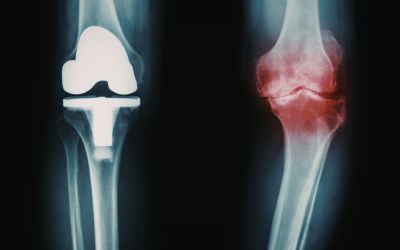

La Medicina Física y Rehabilitación es la especialidad médica a la que concierne el diagnóstico, evaluación, prevención y tratamiento de la discapacidad encaminados a facilitar, manetener o devolver el mayor grado de capacidad funcional e independencia posible.